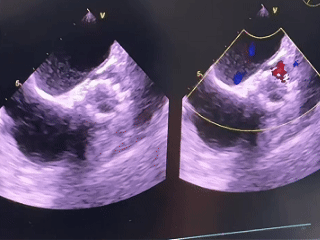

术中超声检查

无明显反流

即刻峰值流速1.48m/s,压差8.74mmHg

术前术后超声对比

20260105→20260117

峰值流速:5.8m/s→1.9m/s

平均压差:83mmHg→7mmHg

二尖瓣反流:2.7cm2→1.0cm2